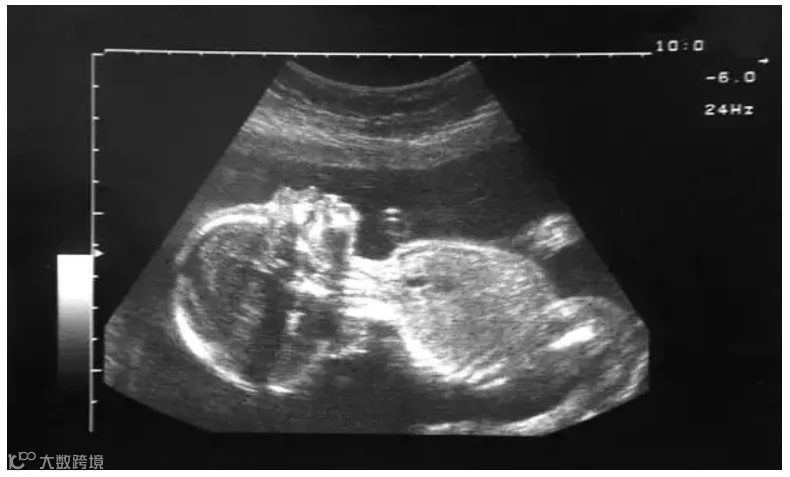

一般胎儿的性器官分化是在怀孕的前三个月。如果“转胎药”中含有大量的雄激素,将会导致女婴男性化或者女性假两性畸形。这也就是人们常说的“阴阳人”,外表看可能会让人觉得是男孩,但孩子的基因并没有改变。

XX女性生殖器男性化照片